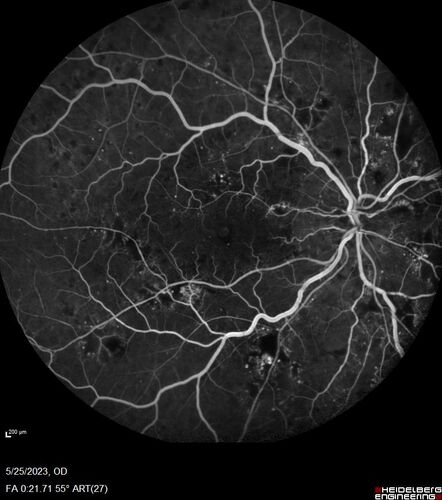

Siegrist Streaks and severe diabetic macular edema

56 year old female who presents four years after developing necrotizing fascitis and multiple organ failure from an infected foot from a roofing nail.  Her vision was 20/100 OU.  She has multiple peripheral pigment spots consistent with Siegrist streaks.